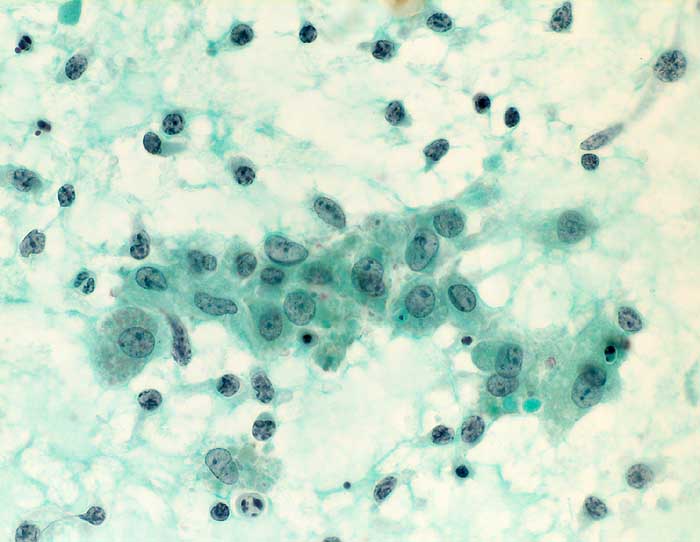

Autoimmun- Sialadenitis bei Sjögren Syndrom

Parotis

Das Zellbild ist je nach Stadium mehr oder weniger zellreich und zusammengesetzt aus Lymphozyten, Myoepithelien und selten Azinuszellen. Ein lymphozytäres Zellbild ist in Kombination mit dem typischen klinischen Bild (Keratokonjunktivitis sicca, Xerostomie, rheumatische Erkrankung) für die Sicherung der Diagnose ausreichend. Auf die Lippenbiopsie kann in diesem Fall verzichtet werden.